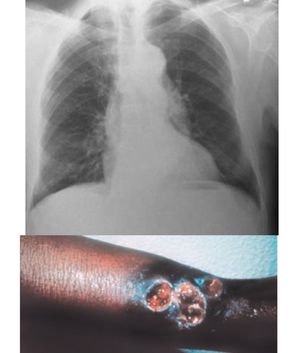

A 45 year old women presents to you with progressive dementia, skin lesion and shortness of breath. Past history of multiple sexually transmitted infections. What is the most likely diagnosis and what is treatment of choice 🤔?

syphilis, possibly, but there may be something more going on, but it explains the lesions